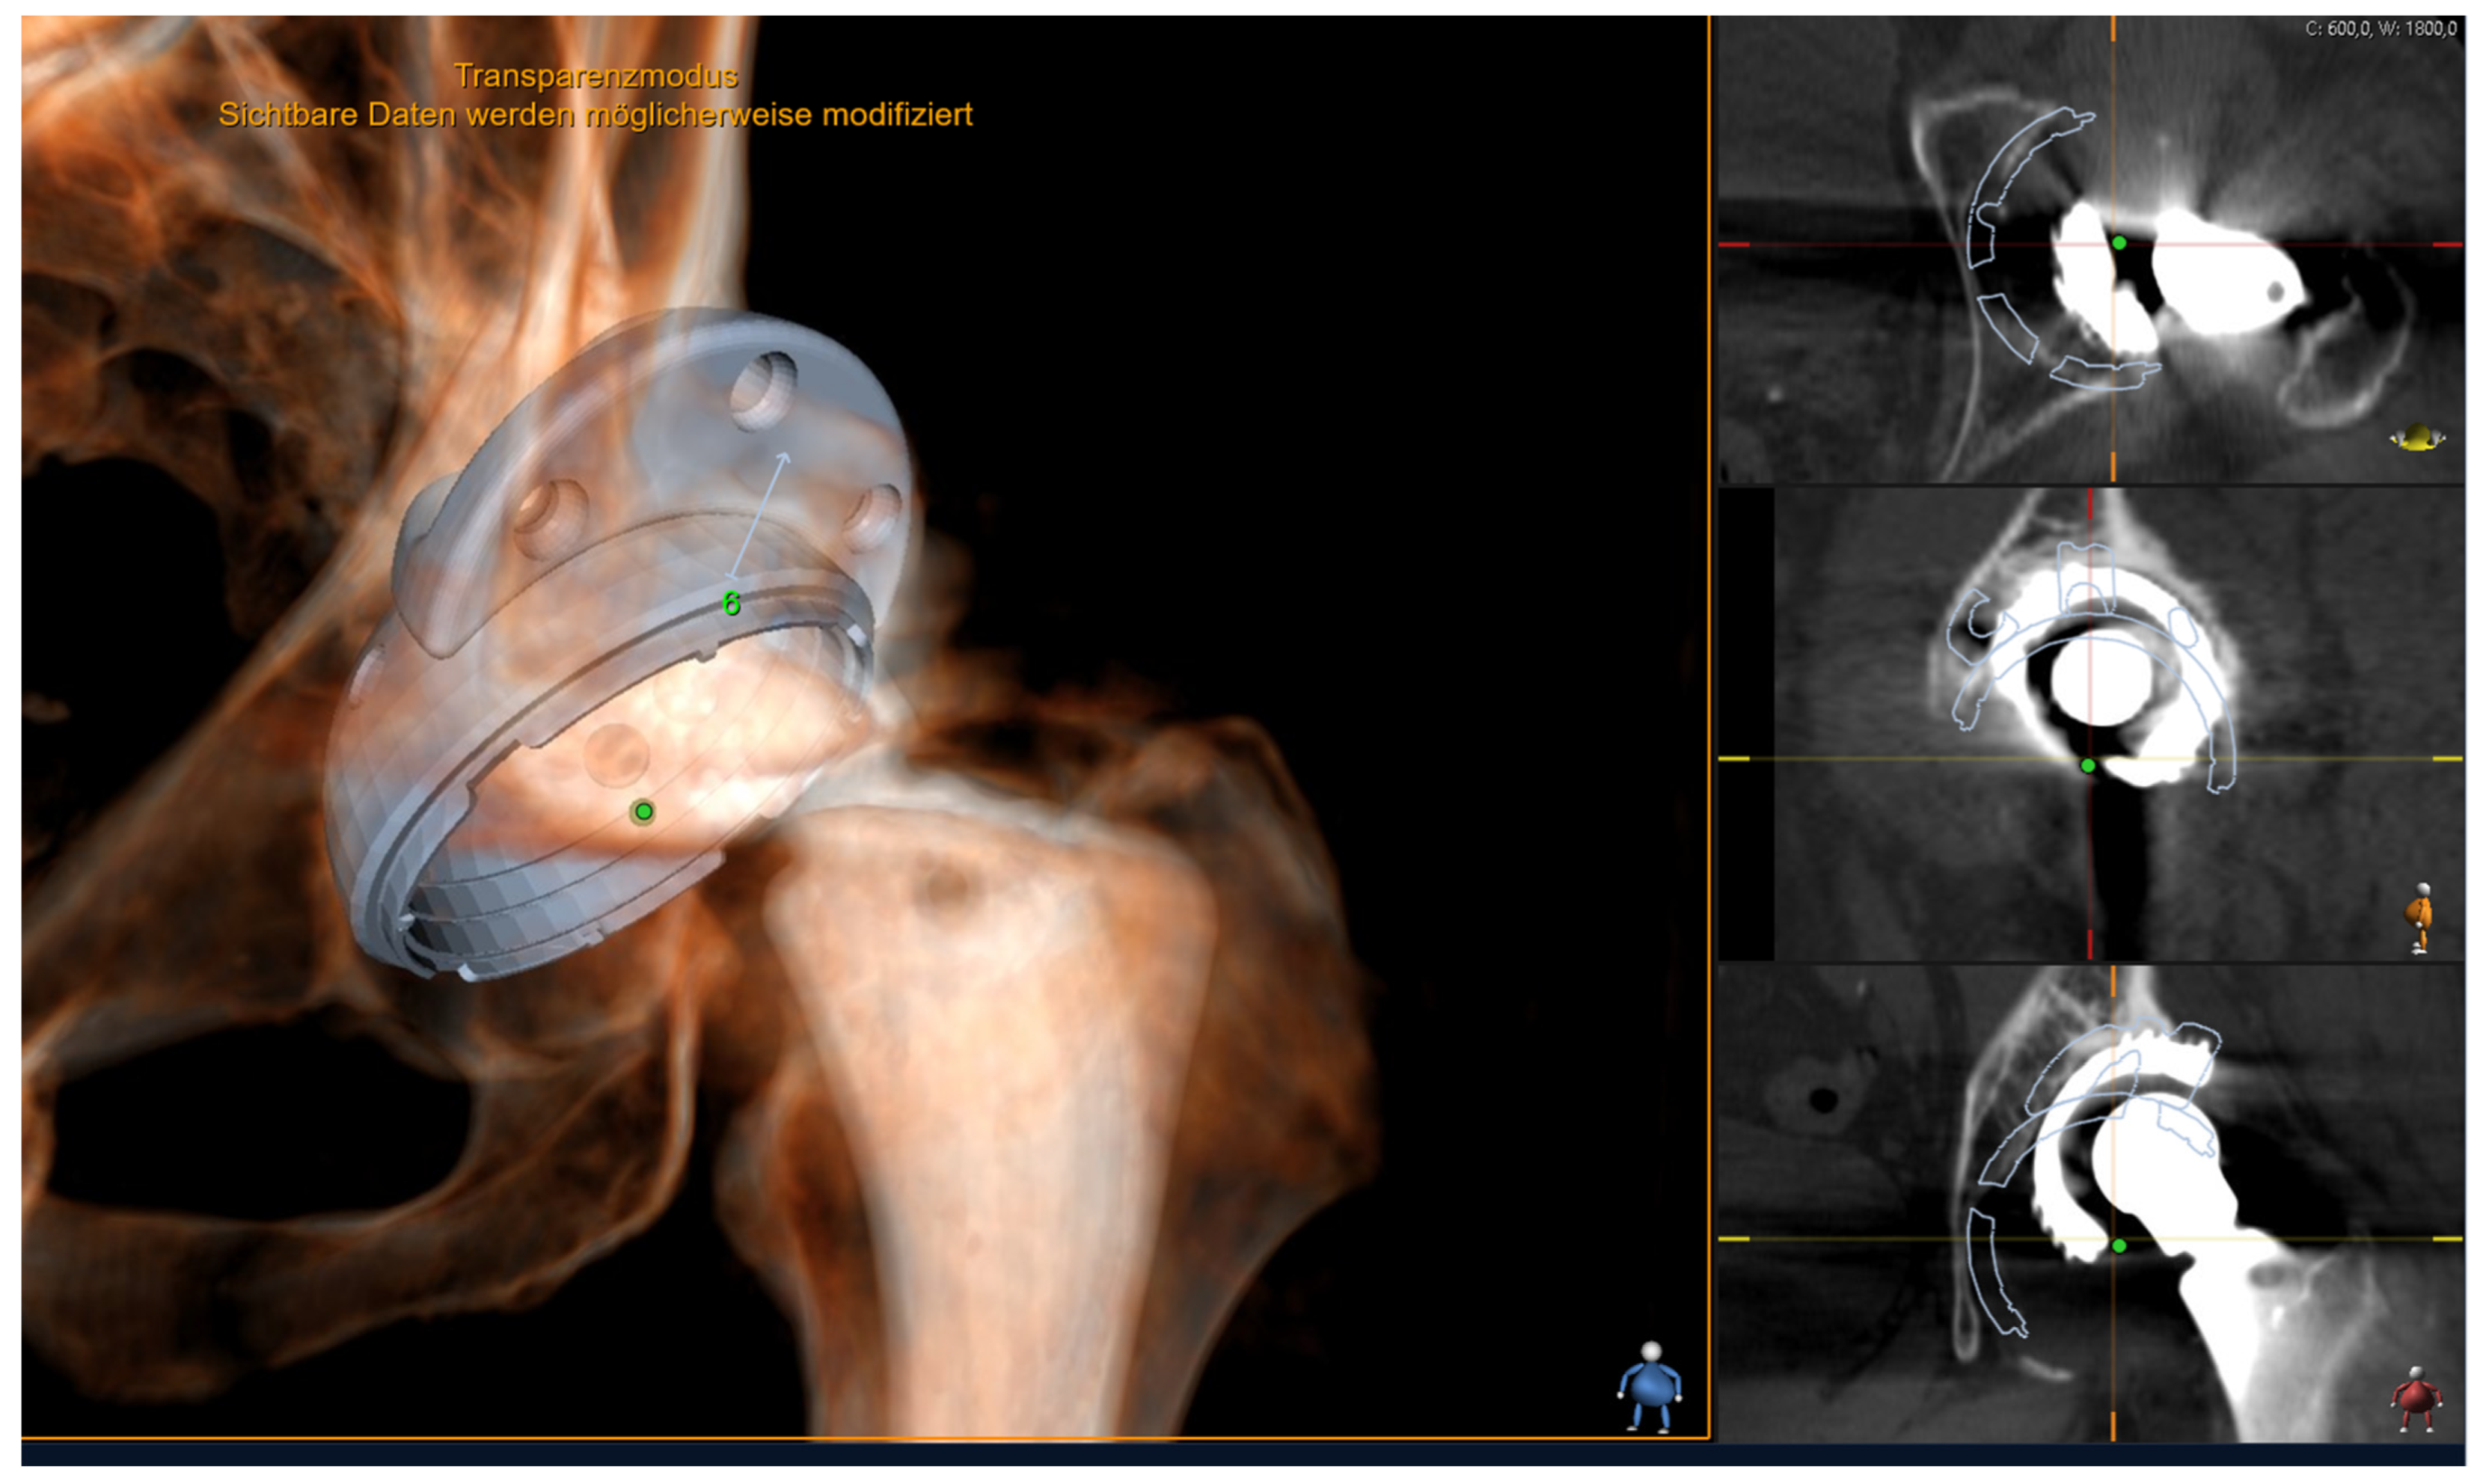

2.2. Digital Templating

Aesculap Plasmafit